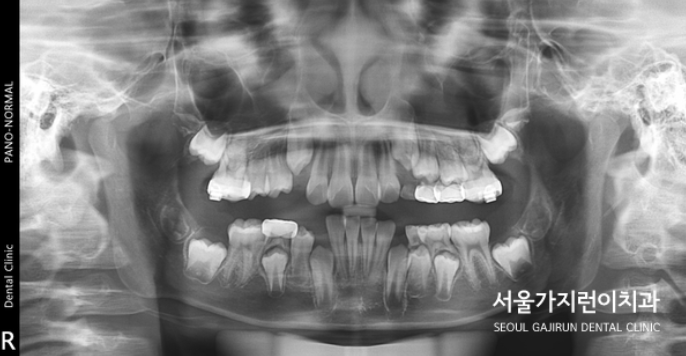

오늘은 상악의 돌출 케이스를 설명해볼텐데요. 치아의 배열 공간이 심하게 부족했던 성장기 환자의 비발치 교정이기 때문에 좀 더 까다로운 교정과정일 수밖에 없었습니다. 환자 분의 경우 상악골의 과성장과 하악골의 열성장이 종합적으로 발현된 케이스로 상악괄의 과성장을 조절하고 상악 견치 및 소구치의 맹출 공간을 확보하기 위해 상악 어금니의 후방이동이 필요했는데요. 그 과정에서 헤드기어라는 장치를 이용한 치아교정이 이루어졌습니다.

이후에는 돌출감을 해소하기 위한 미니스크류를 활용한 치아교정이 이루어졌는데요. (미니스크류는 잇몸에 박혀있는 작은 나사와 같은 장치를 말합니다. ) 미니스크류는 간단한 국소마취로도 식립이 가능하고 잇몸뼈에 직접 식립하기 때문에 강력한 고정힘으로 정밀하게 치아이동이 가능한데요. 치료를 하지 않았다면 치아의 배열이 심하게 비뚤어지고 상악 전치가 뻐드러졌을 것을 1차 성장교정(헤드기어)를 통해 만족할 수 있는 경과를 만들어냈습니다.